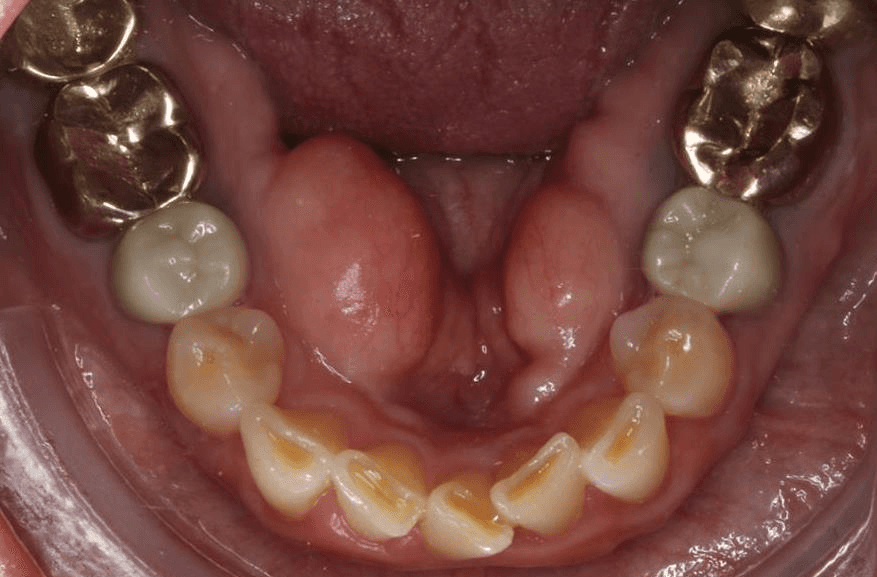

Diganosis: Complex pre-restorative treatment to open bite, mild to moderate upper and lower crowding, incisal wear in both arches

Adjuncts: Bite ramps, attachments, IPR

INTRAORAL